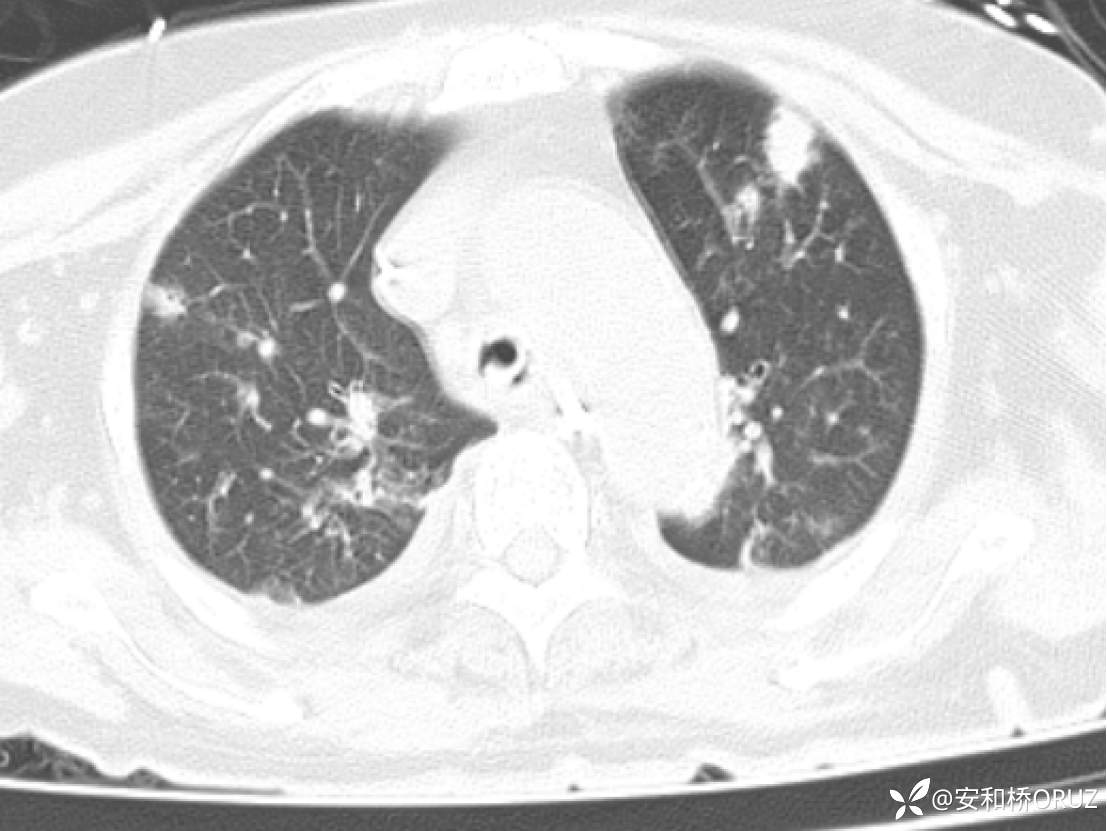

两肺见散在斑点、结节状、片状高密度影,部分界欠清